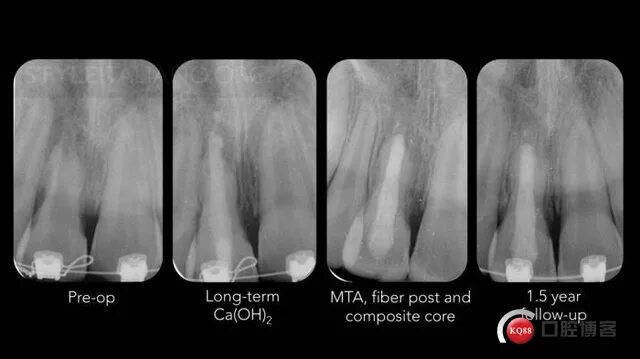

Признаки резорбции